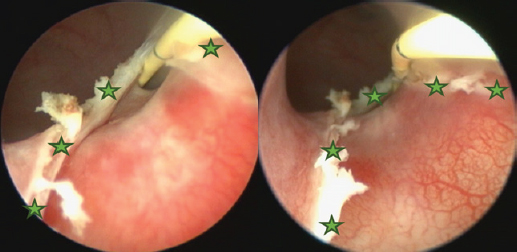

The surgery aimed to cut the outer ureteral membrane and redirect left kidney-produced urine from the urethra to the bladder. Before cutting, a hydrophilic 3 Fr catheter was introduced through a pathologic left ureter opening. It worked as a guide to fully visualize the intramural ureteral tunnel. After that, a Karl Storz monopolar coagulating ball electrode (3 Fr × 53 cm) was introduced through the working channel of the cystoscope sheath. The electrode cut the medial aspect of the ureteral wall up to the bladder trigone, where the contralateral normal ureter opens. The cut membrane did not bleed during the surgery (Figs. 68).

Fig. 6. Cystoscopy picture where the ureteral membrane (see the green stars) is seen before cutting with the semirigid Karl Storz monopolar coagulating ball electrode (marked with a red arrow). A bright yellow 3 Fr guide catheter is seen on the right side of the picture (marked with a yellow arrow).

Fig. 7. Cystoscopy pictures where green stars indicate edges of the cut ureteral membrane. A yellow 3 Fr guide catheter is seen on the right side of both pictures.